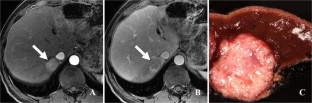

Fig. 3